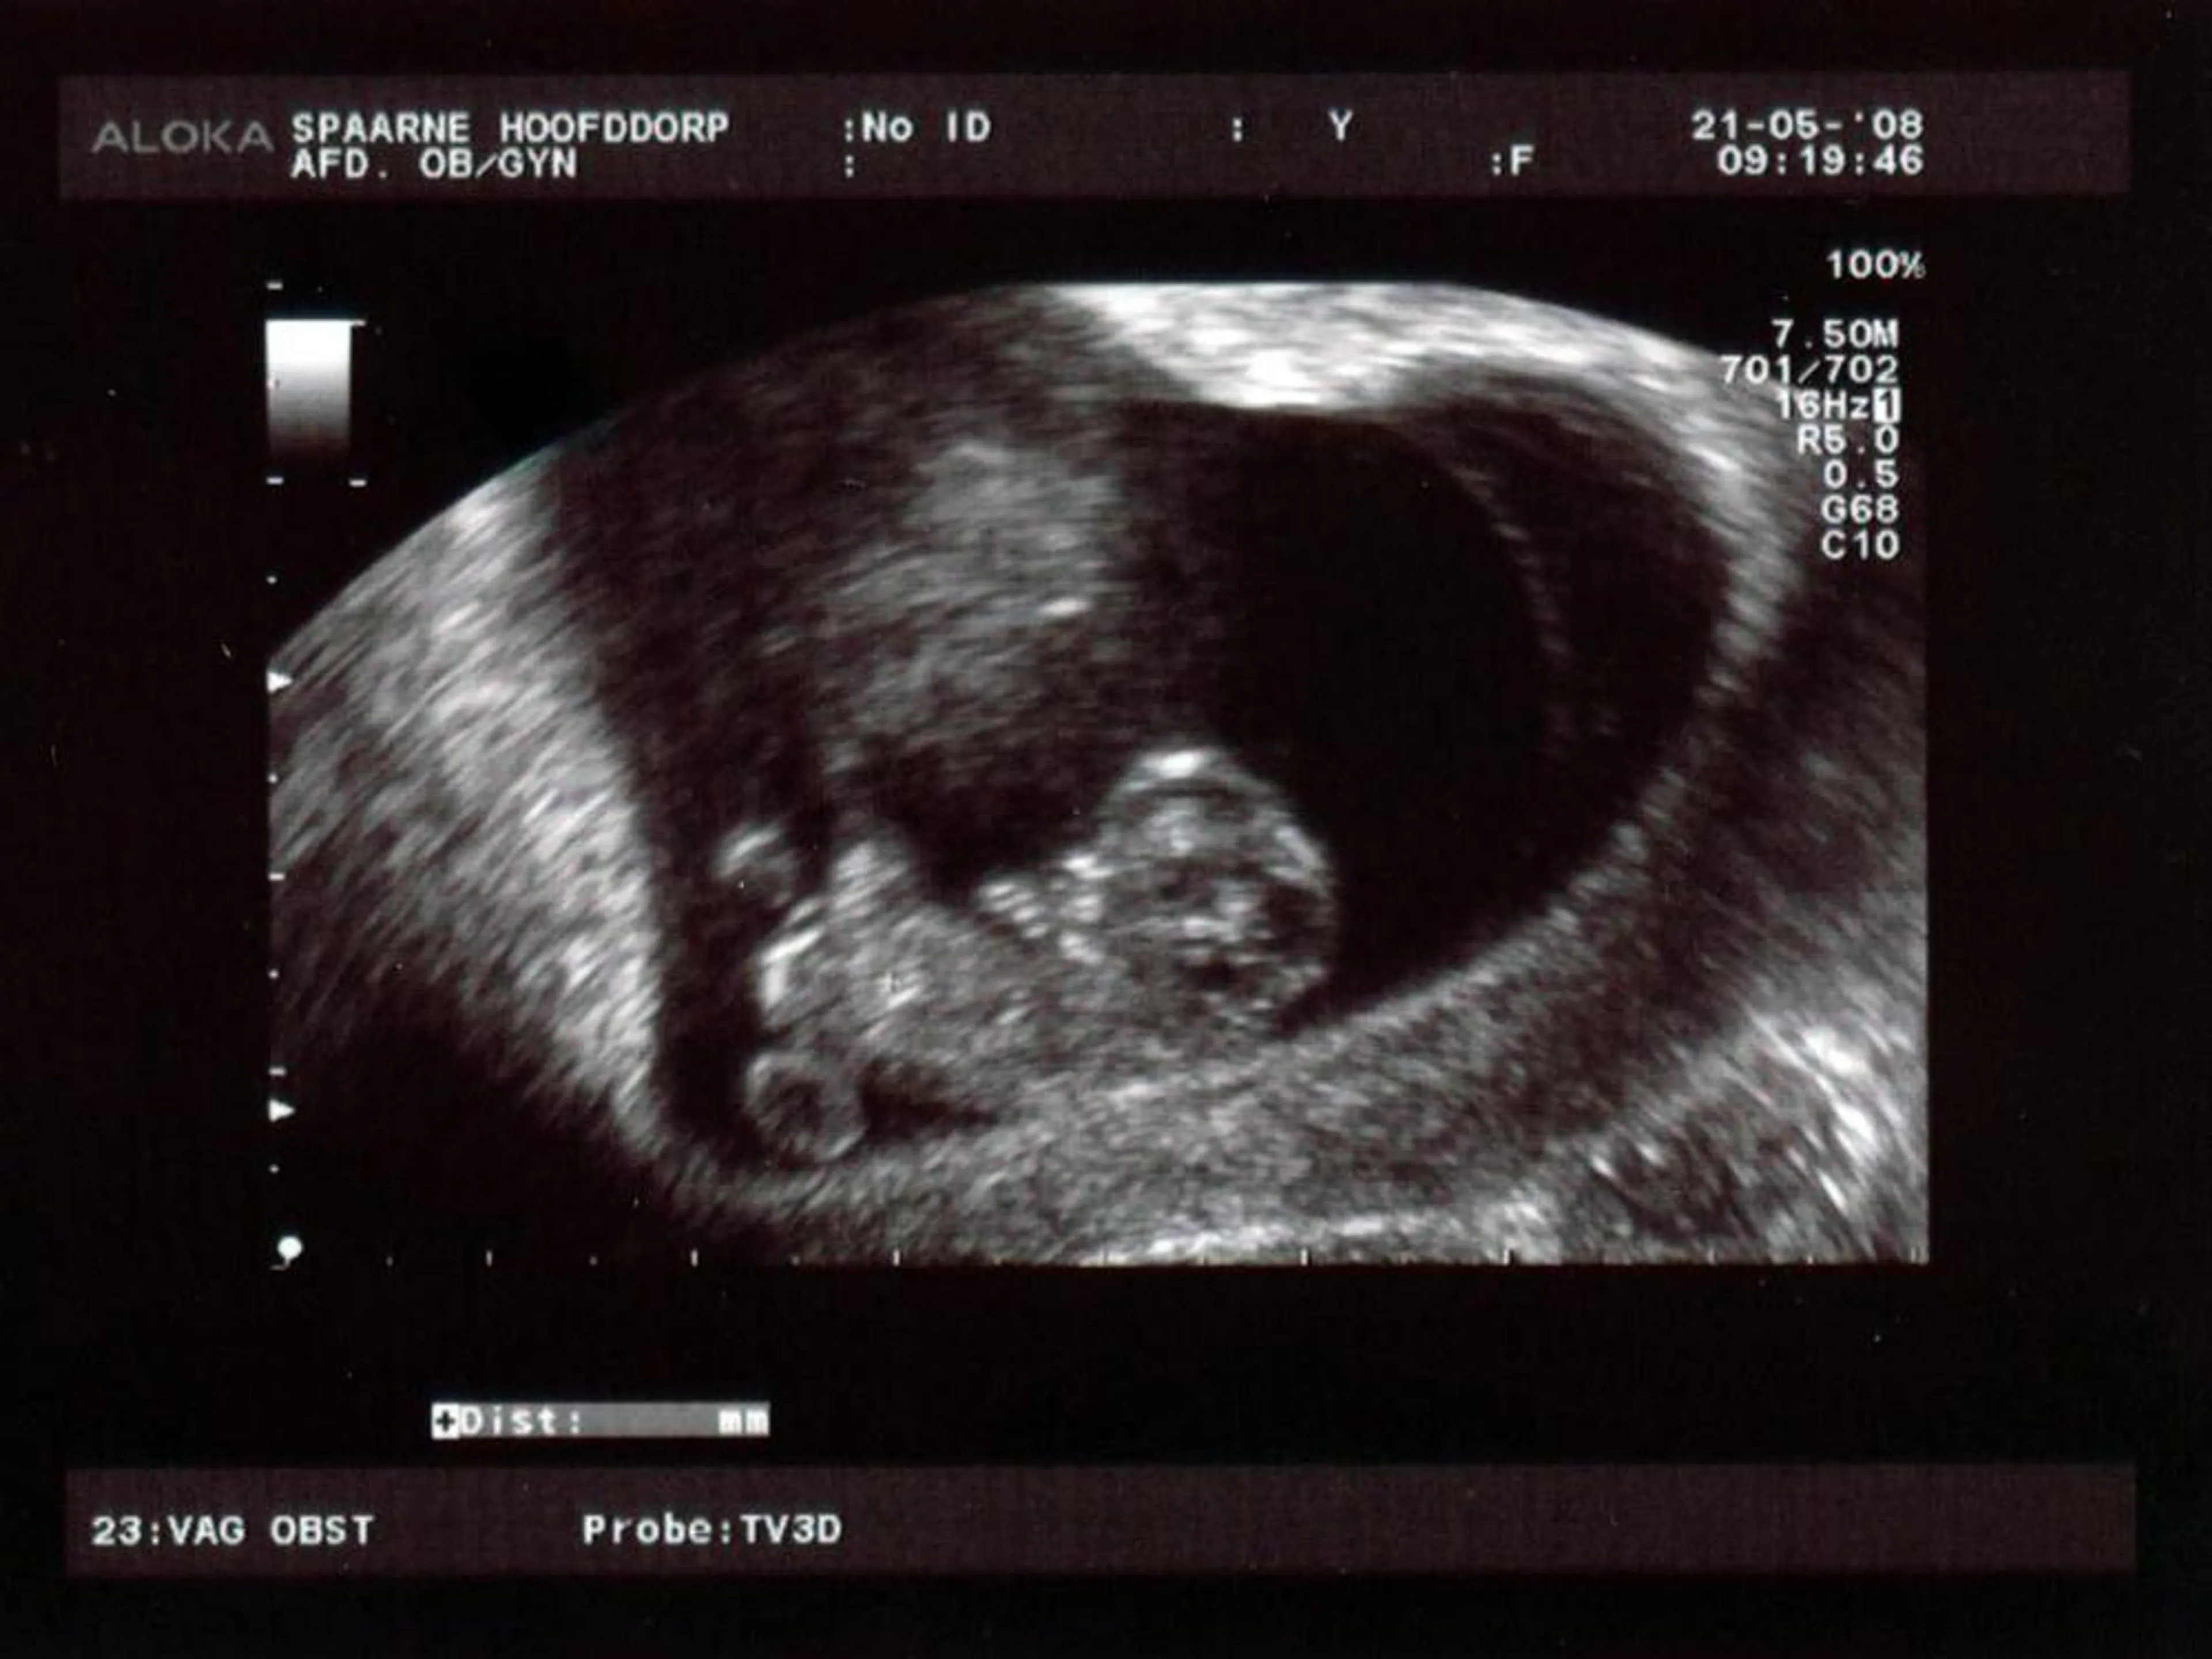

Dat is dan ook tegelijk een reactie op een tweede veronderstelling die je maakt, namelijk dat die ziel óf bij de bevruchting óf bij de geboorte erin moet komen. Nu zijn er veel meer opties dan die beide, denk ik, maar vooral: er is niet één moment, maar de ziel ontwikkelt zich langzamerhand. Ons karakter, leven, geest is er al heel pril in de eerste weken van een embryo en wordt langzamerhand steeds complexer en ‘echter’.